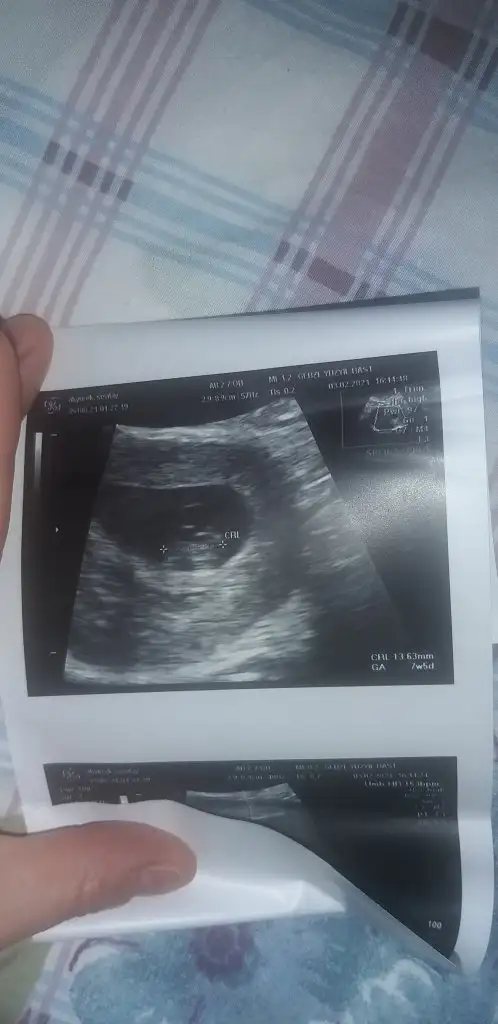

Bana da yapabılır mısınMaşallah çok tatlı bir bebişcanım ben ramzi teorisine göre bakıyorum eğer ki 6-8. Haftalar arasında ultrason görüntüsü varsa ordan plasenta konumuna göre bir yorum yapabilirim

Bana kız gibi geldi canımTeşekkür ederiz canım benim hemen atıyorum 7+5Eki Görüntüle 2791786 Eki Görüntüle 2791786